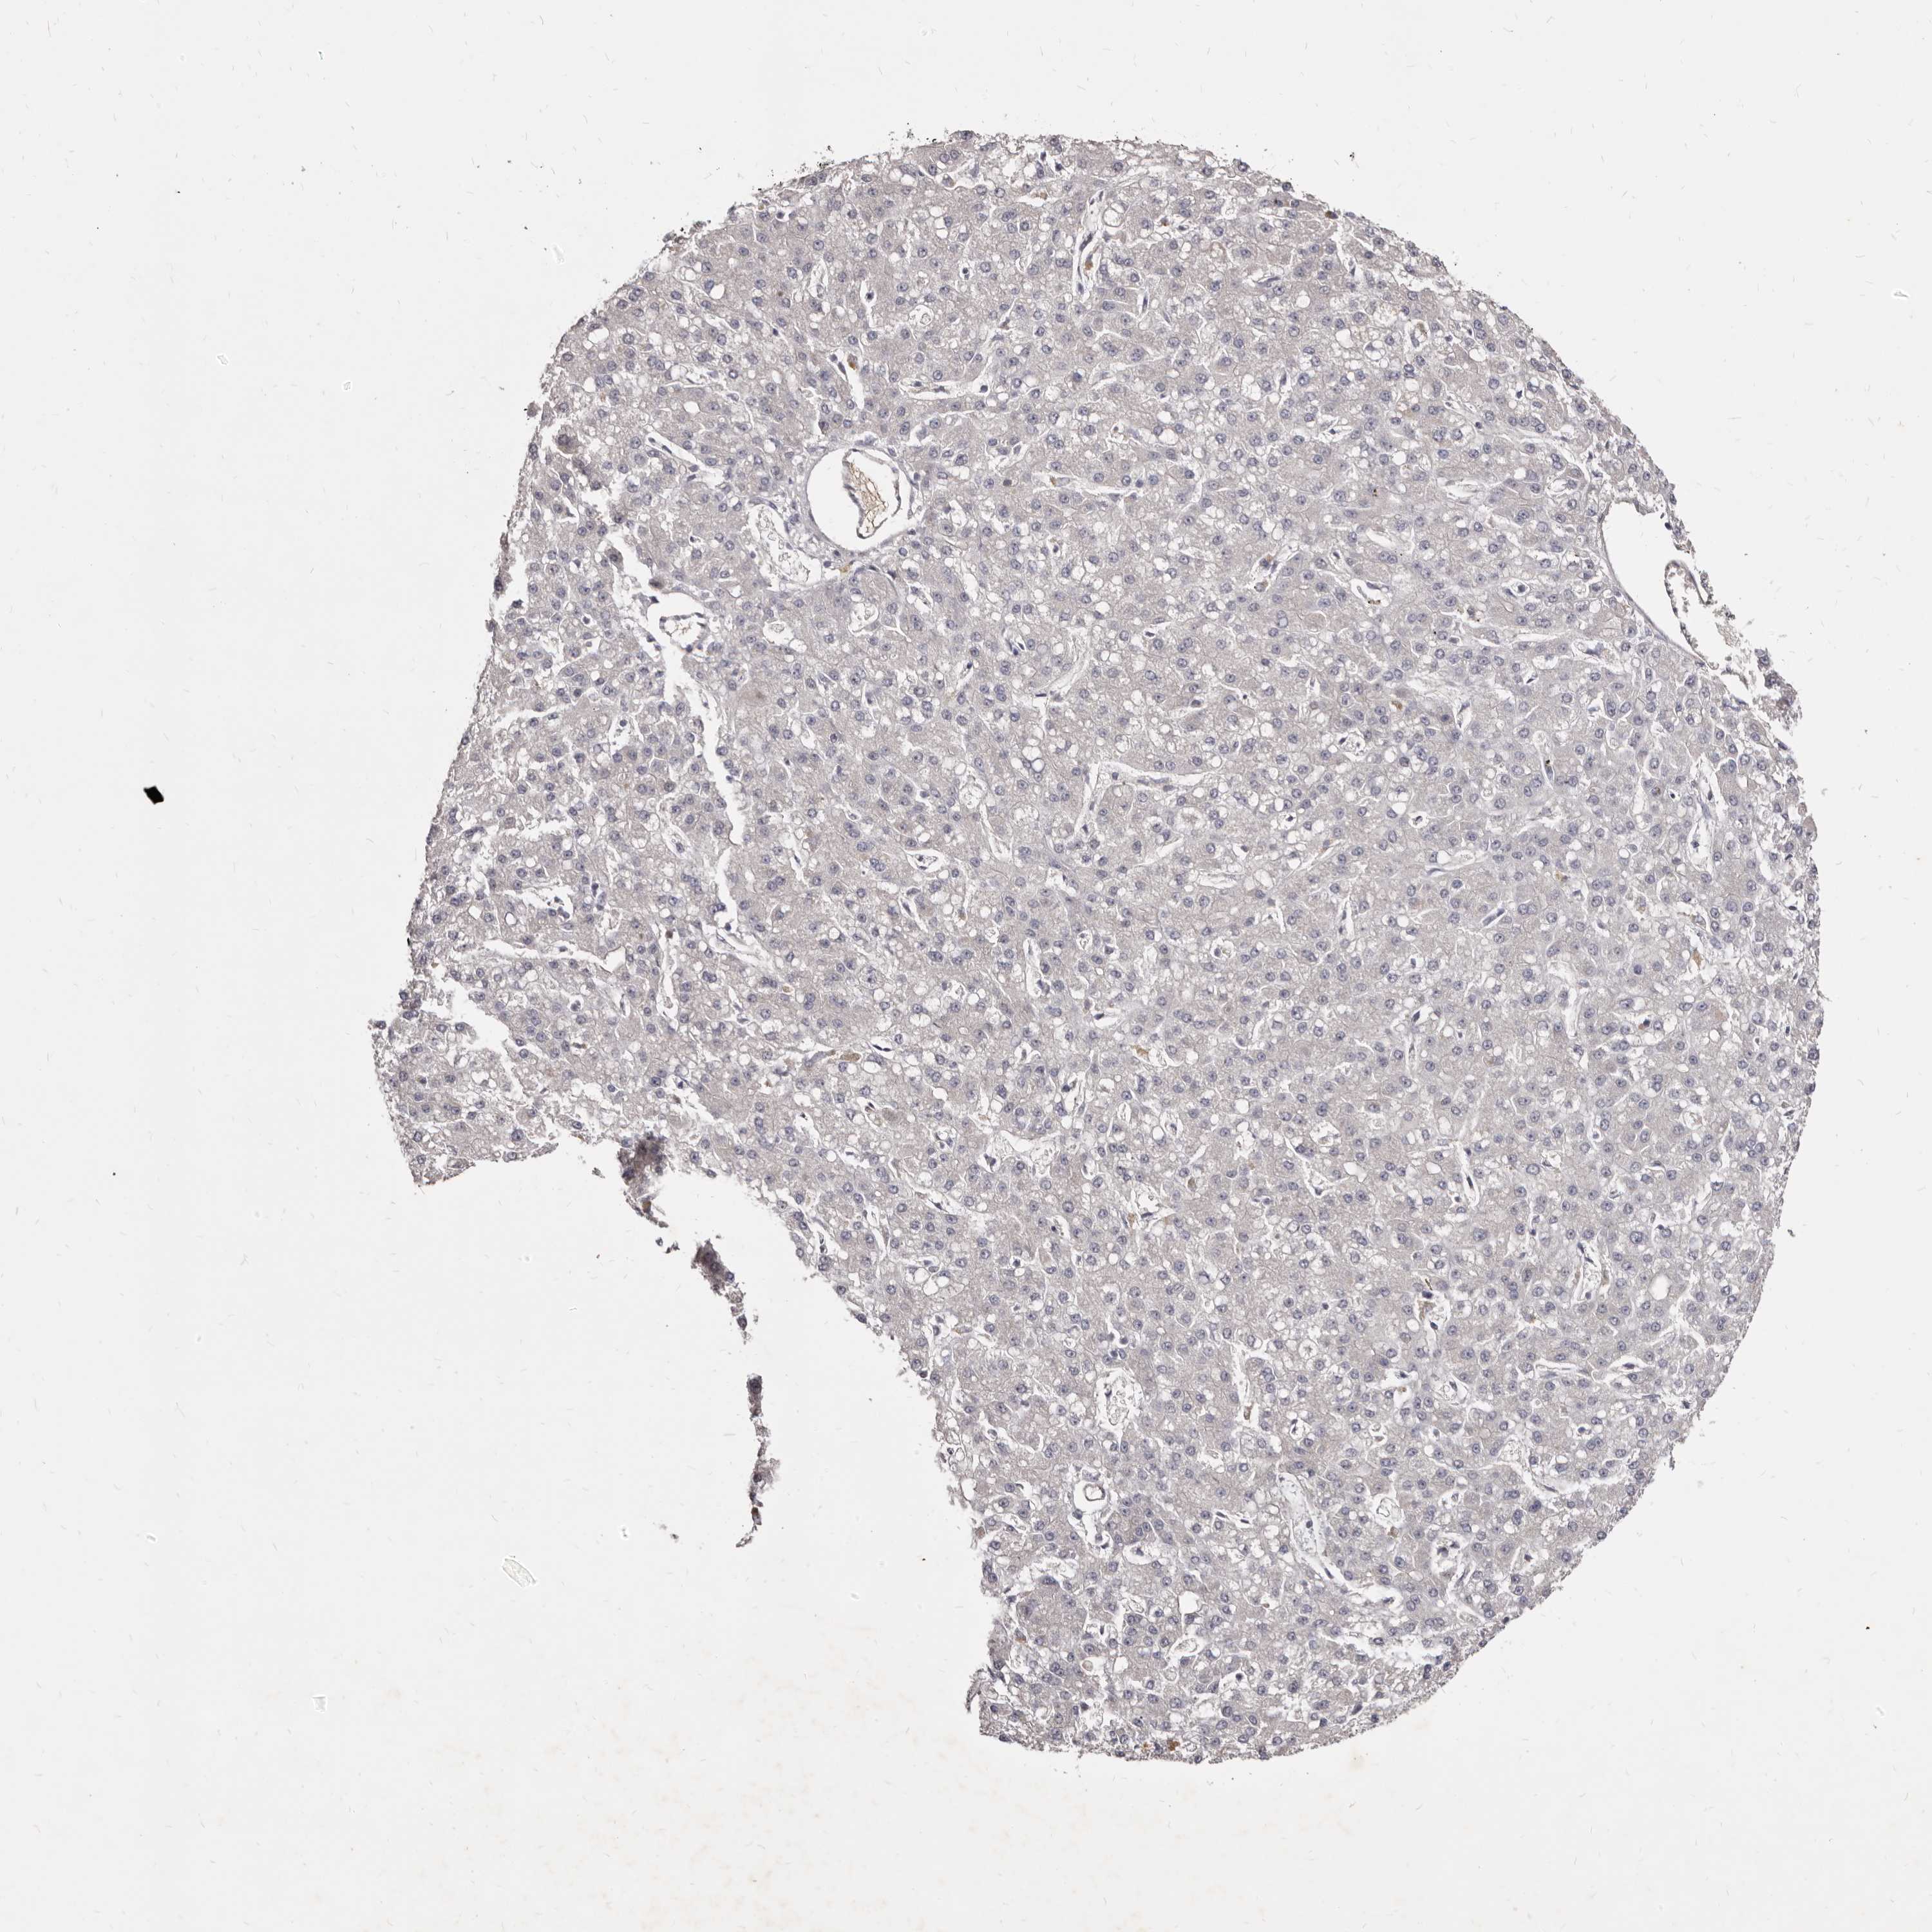

LIVER CANCER - Protein expressioni

A mouse-over function shows sample information and annotation data. Click on an image to view it in a full screen mode. Samples can be filtered based on level of antibody staining by selecting one or several of the following categories: high, medium, low and not detected. The assay and annotation is described here.

Note that samples used for immunohistochemistry by the Human Protein Atlas do not correspond to samples in the TCGA dataset.

Antibody stainingi

Antibody staining in the annotated cell types in the current human tissue is reported as not detected, low, medium, or high, based on conventional immunohistochemistry profiling in selected tissues. This score is based on the combination of the staining intensity and fraction of stained cells.

Each image is clickable and will lead to virtual microscopy that enables deeper exploration of all samples and also displays staining intensity scores, fraction scores and subcellular localization as well as patient and tissue information for each sample.

Antibody HPA023081

Antibody HPA023103

Antibody HPA024795

Staining

High

Medium

Low

Not detected

Intensity

Strong

Moderate

Weak

Negative

Quantity

>75%

75%-25%

<25%

None

Location

Nuclear

Cytoplasmic/membranous

Cytoplasmic/membranous,nuclear

Cholangiocarcinoma

Carcinoma, Hepatocellular, NOS